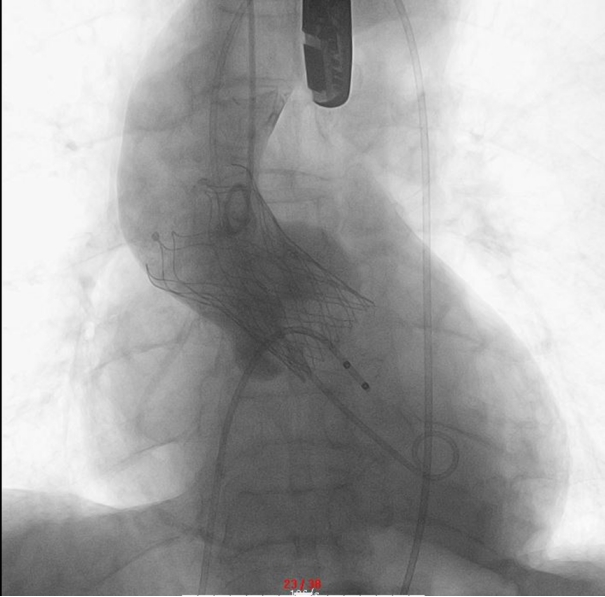

▲ 术后主动脉根造影:瓣膜完全释放后造影示无返流,无跨瓣压